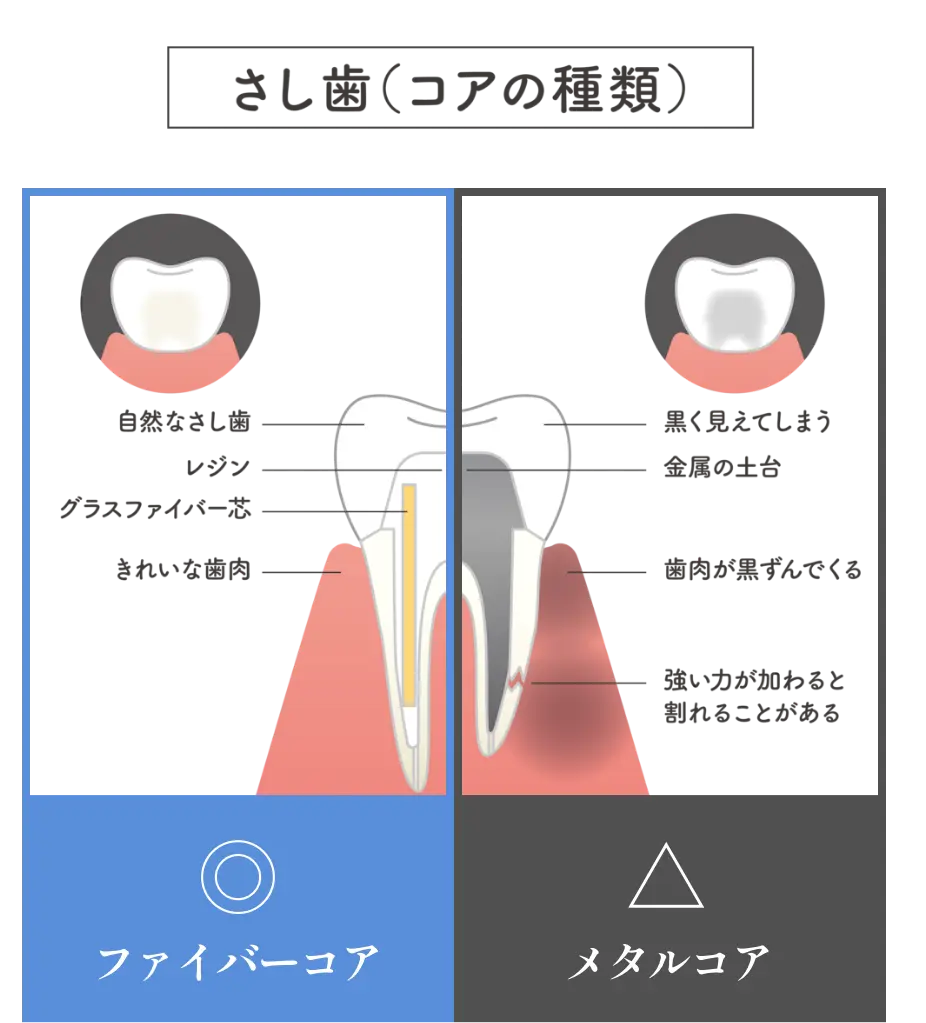

神経のない歯には、金属を使用しない「ファイバーコア」で

金属アレルギーや歯ぐきの変色を予防し、長持ちする土台を

「ファイバーコア」です

通常は神経のない歯にいれるコア(土台) はハイブリッドと金属の芯を用いてメタルコア(土台)で作られます。ただこのメタルコアは金属のため錆びてしまったり、溶け出した成分で歯や歯ぐきが変色することがあります。

また最大の問題は、歯と金属の柔軟性や堅さが異なることで「くさび」の様に作用して、根管治療をした大切な歯を割ってしまう歯根破折のリスクが高い点です。

当院ではこのコア(土台) の素材として「ファイバーコア」を推奨しております。金属を全く使用しないい素材であるファイバーコアは弾性(しなやかさ)があり、衝撃を吸収する特性もあるため歯を割ってしまうリスクを低減します。

白色で光を透過するので、被せ物の白い歯も自然な透明感となります。金属を一切使用しないファイバーコアは金属アレルギーの心配もありません。このようにファイバーコアは歯とからだに優しい歯科治療の土台となる素材です。